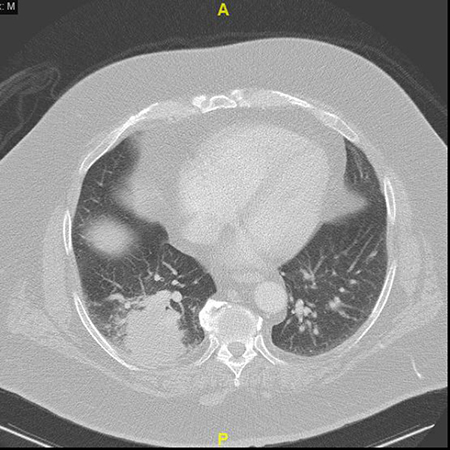

Clinical History:A 59-year-old man with a history of melanoma presented with a 1.6-cm endobronchial mass. The mass was biopsied and diagnosed as metastatic melanoma, and he subsequently underwent mass debulking and systemic therapy with checkpoint blockade therapy. Eight months later, the patient complained of cough and shortness of breath. A CT chest was notable for a right lower lobe mass (5.6 cm; Figure 1), clinically suspected to represent progressive melanoma. The patient otherwise had no other systemic evidence of progressive metastatic melanoma, therefore the patient underwent resection of the lung mass (Figures 2-6).